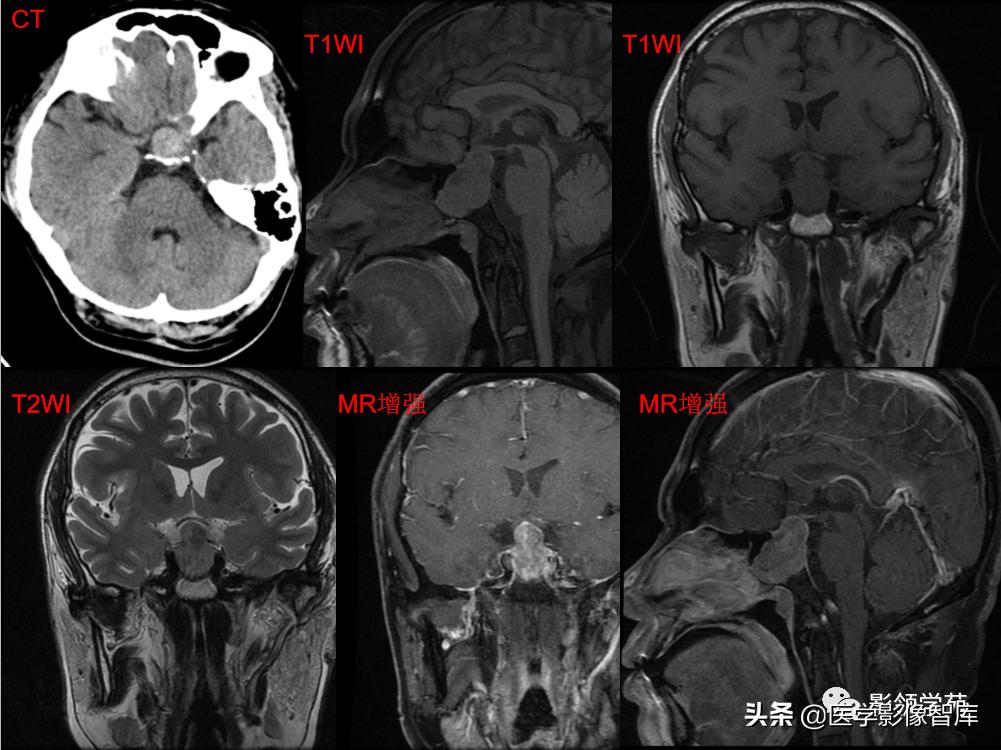

男,2岁,双视力障碍

鞍区见一类圆形囊性肿块,呈长T1长T2信号,囊壁厚薄不均。

囊壁呈环状强化,囊内未见明显强化。病灶占据蝶鞍、鞍上池及第三脑室前部,边缘清楚。

鞍区见一类圆形囊性肿块,囊壁呈蛋壳样钙化。肿块向下压入蝶鞍,向上达到第三脑室水平。

男 17岁,语言异常、视力减退、尿*禁失**、昏睡1月余。

鞍上池-第三脑室见一类圆形囊实性占位,边界清晰,内部以囊性长T1、长T2信号为主,信号均匀;另在囊下壁可见多发结节状实性病灶,呈乳头状向囊内凸起。

囊内实性病灶及囊壁明显强化,囊内容物无强化。视交叉受压向前移位,垂体可见,但垂体柄显示不清。中脑结构向后移位,中脑导水管通畅。

第三脑室明显变窄,双侧侧脑室、第四脑室外形正常。肿块邻近脑实质呈受压改变,关系清楚,无脑实质浸润及水肿信号。

(压迫视交叉、垂体柄、中脑;无梗阻性脑积水)